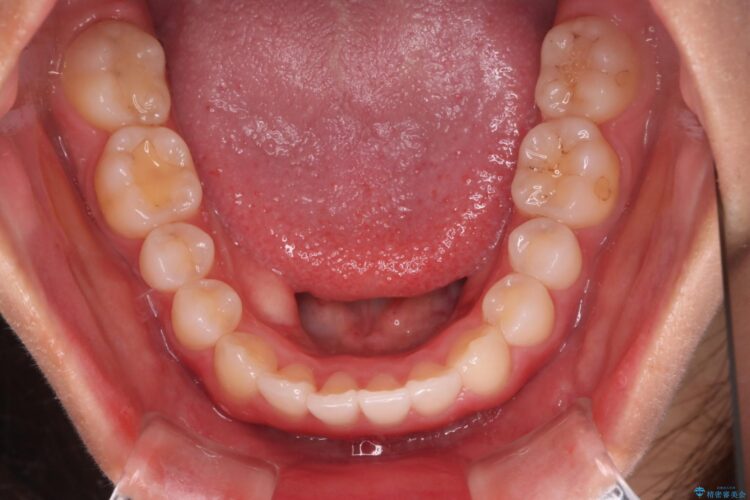

下の前歯のガタつきと正中のズレが気になるとご来院された患者様です。

軽度のガタつきだあったのと、かみ合わせがやや深かったため、インビザラインで治療を行うこととしました。

IPR(歯と歯の間を削る処置)と歯列拡大をすることでガタつきをとります。

前歯のガタつきを改善するのに時間がかかりましたが、ガタつきもかみ合わせも綺麗になりました。